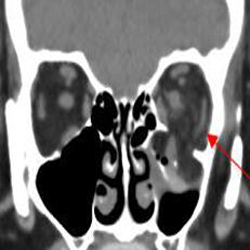

Nasolacrimal Canal and Sac

There is bony injury to the nasolacrimal canal.

The nasolacrimal sac appears to be intact.

Fronto-Naso-Ethmoidal Complex

The mesial naso-orbito-ethmoid complex is fractured. Specifically, there is bony injury of the nasal bones or the frontal process of the maxilla and the medial walls of the orbit are abnormal.

The intercanthal distance is increased.